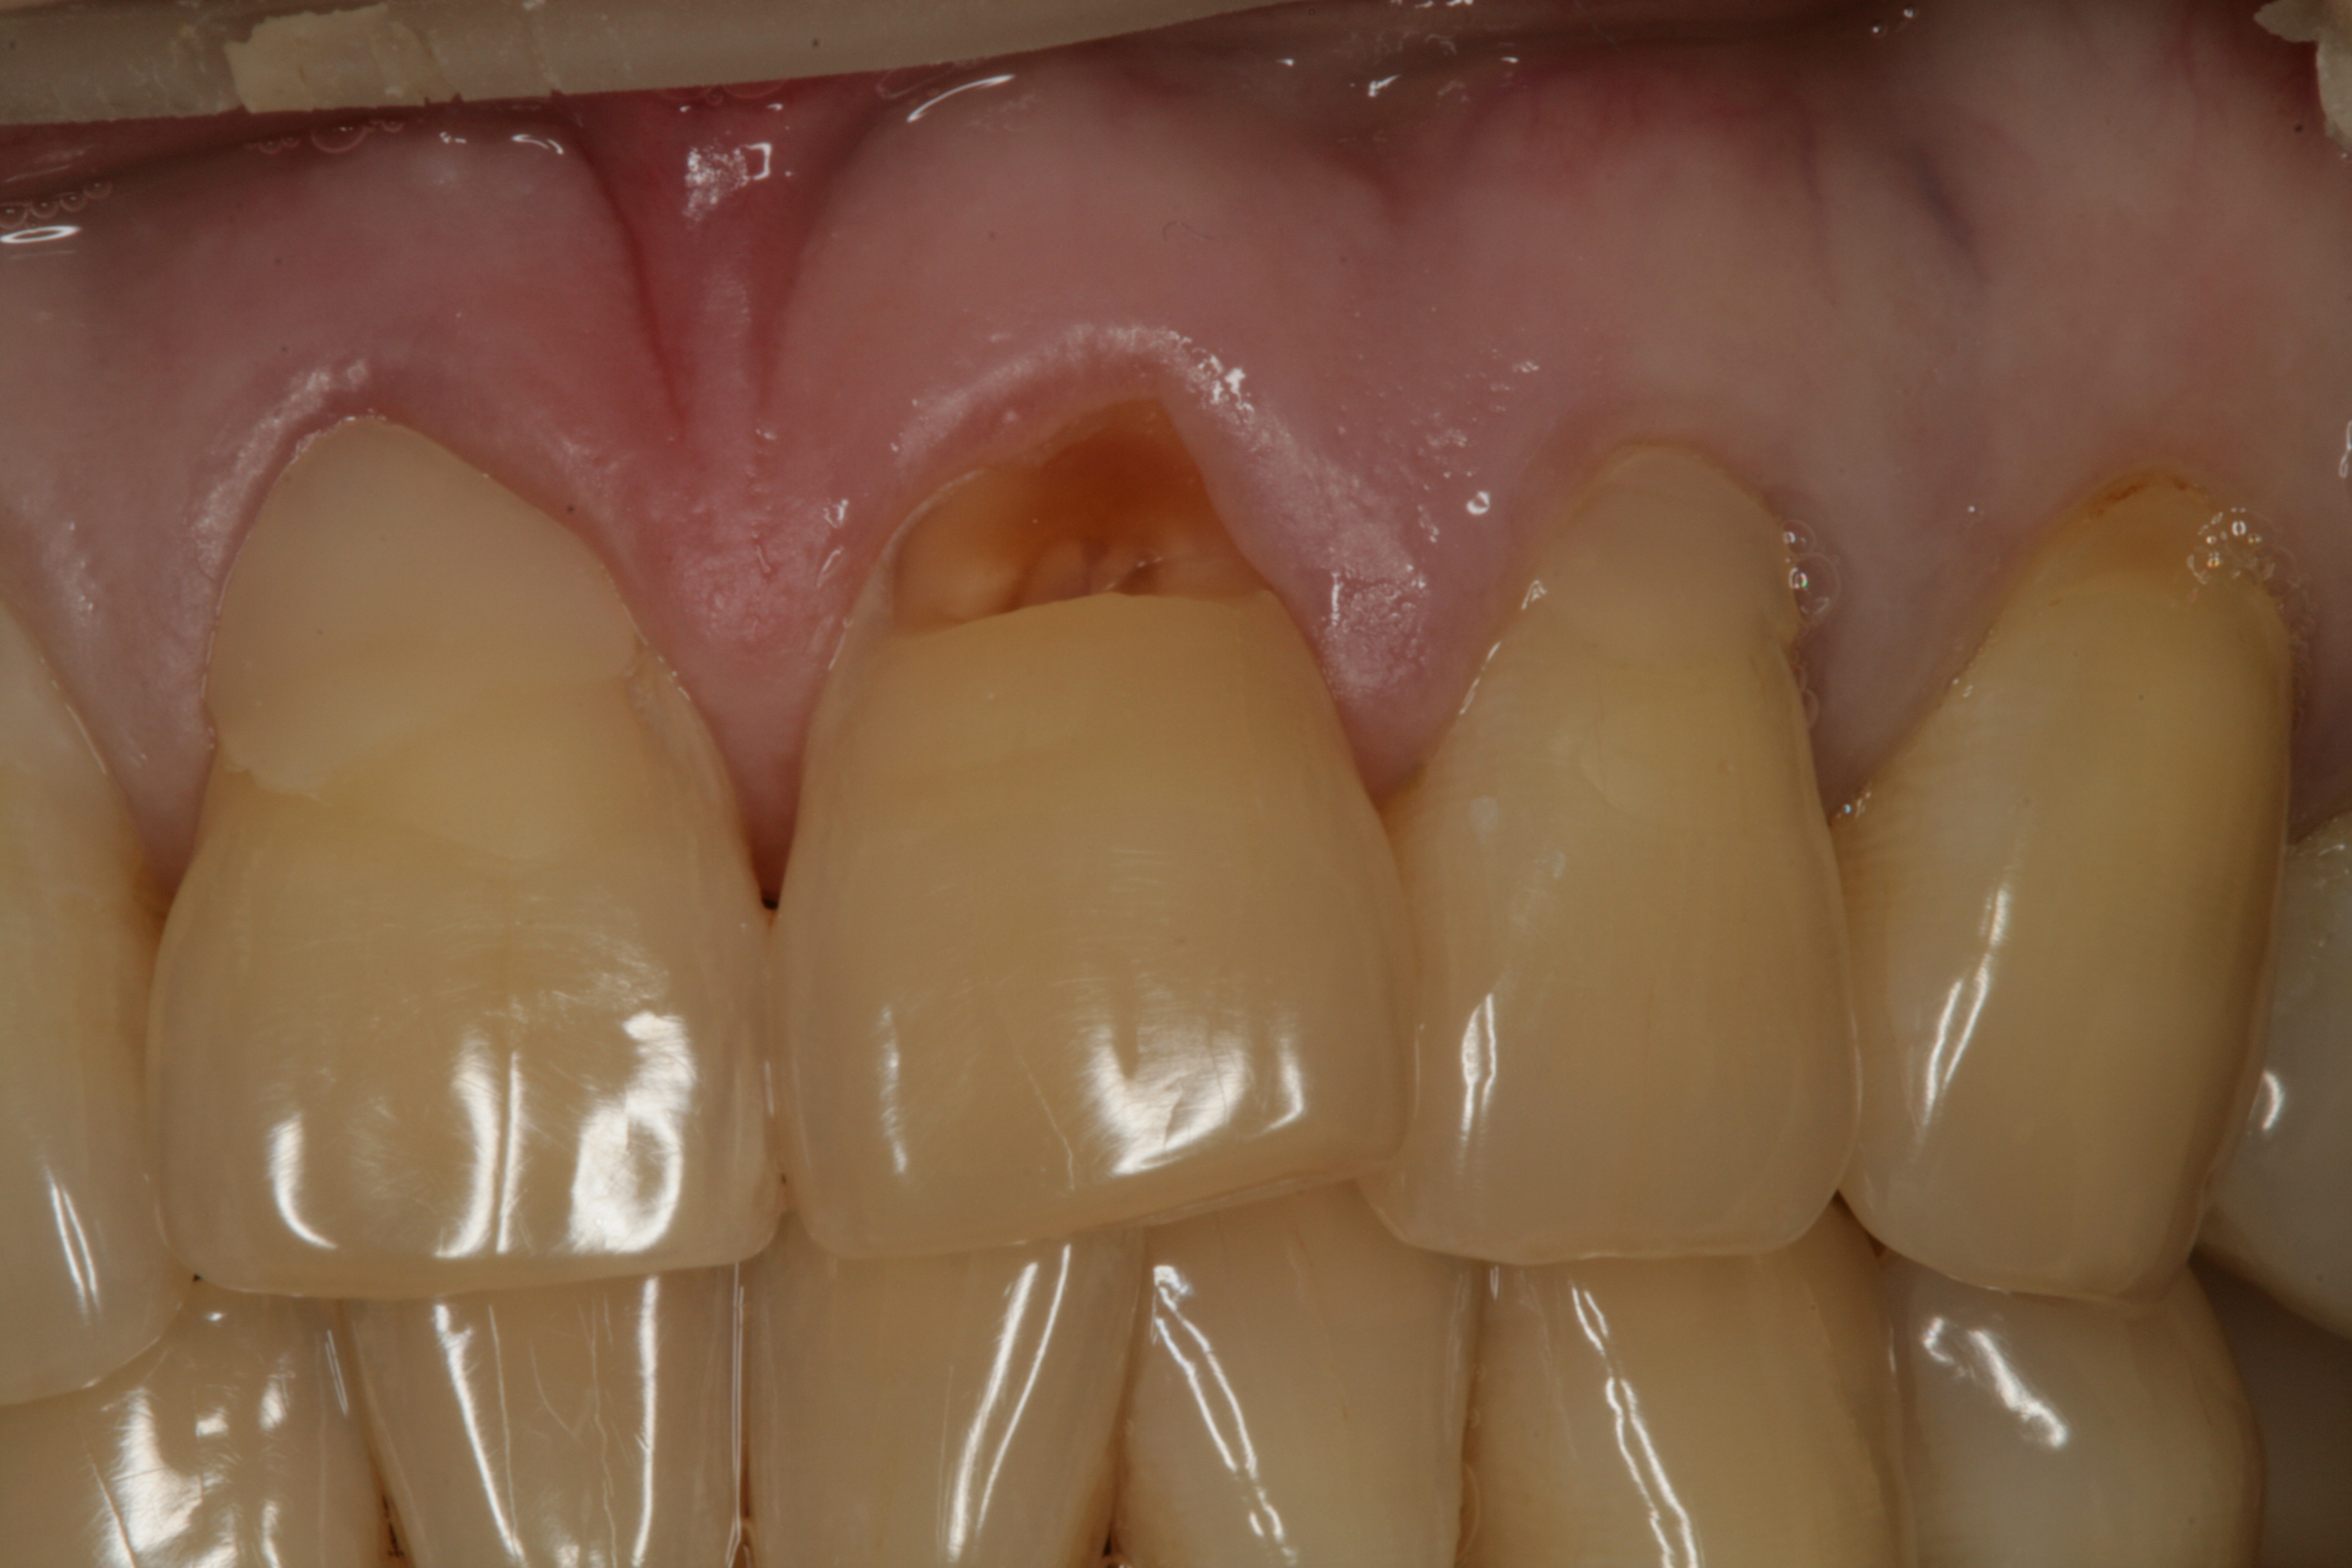

이렇게 패인 치아를 계속 방치할 경우 신경까지 노출되어 부득이하게 신경치료를 해야하는 경우도 있고

경우에 따라서는 저작할 때마다 받는 교합력을 남은 치질만으로 견뎌야하기 때문에 치아가 부러질 수도 있습니다.